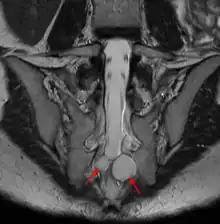

Un kyste de Tarlov (KT) ou kyste périneural, est une dilatation locale de l'espace sous-arachnoïdien se formant au contact d'une racine nerveuse, le plus souvent sacrée, dans la zone de transition entre arachnoïde et périnèvre (membrane externe du nerf). Il est fréquent et le plus souvent asymptomatique, mais peut parfois causer des symptômes neurologiques : on parle alors de maladie de Tarlov.

La cavité kystique correspond à une prolongation de l'espace sous-arachnoïdien entre l'endonèvre et le périnèvre. Dans la classification de Nabors (1988) les KT correspondent à des kystes de type II[2]. Génétiquement, ils sont rattachés à la famille des défauts du tube neural[3],[4].

Le kyste de Tarlov est le plus souvent asymptomatique et découvert fortuitement lors du bilan d'imagerie d'une lombosciatique[5]. Cependant le kyste en lui-même peut être une cause de sciatique, voire lorsqu'il est situé au niveau sacré de troubles vésicosphinctériens (mictions impérieuses, dysesthésie anale...)[5]. Chez la femme, le kyste de Tarlov peut être la cause d'un syndrome d'excitation génitale persistante[6].

Quel que soit le système de classification, la définition d'un kyste de Tarlov est histopathologique car elle nécessite la présence de fibres de racines nerveuses de la colonne vertébrale dans la paroi du kyste ou dans sa cavité. Les kystes de Tarlov sont définis comme des lésions sacciformes, remplies de LCS, situées dans l'espace extradural du canal spinal sacré et formées à l'intérieur de la gaine de la racine nerveuse au ganglion de la racine dorsale.

Les kystes ont une paroi composée de périnèvre et de tissu neural. Ils montrent une paroi des tissus membraneux, avec des fibres nerveuses périphériques et les cellules ganglionnaires intégrés dans le tissu conjonctif. Ils ont trouvé des fibres nerveuses dans les parois des kystes dans 75 % de leurs cas.